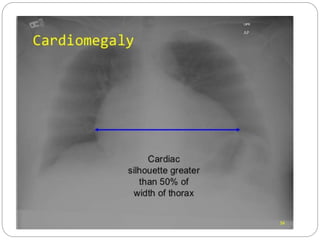

IMAGING STUDIES

 Chest roentgenography :

Cardiomegaly, pulmonary congestion, and

other findings consistent with heart failure

may be seen on chest radiography.